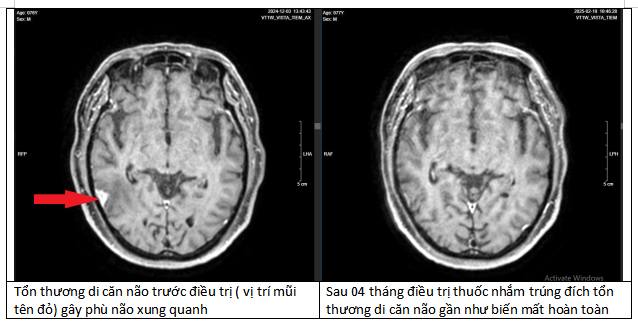

Kết quả MRI sọ não xuất hiện tổn thương nghi ngờ ác tính do di căn. Để tìm căn nguyên, bệnh nhân đã được tầm soát toàn cơ thể.

Theo Thạc sĩ, bác sĩ Nguyễn Duy Anh, Trung tâm Ung bướu, Xạ trị và Y học hạt nhân Quốc Tế (Bệnh viện Đa khoa Phương Đông), kết quả kiểm tra cho thấy bệnh nhân mắc ung thư phổi giai đoạn cuối, di căn xương, di căn não.

Kết quả xét nghiệm gen cho thấy bệnh nhân có đột biến dương tính với ALK. Đây là một đột biến hiếm nhưng có thể điều trị hiệu quả bằng thuốc nhắm trúng đích.

Sau 4 tháng điều trị, các khối u tại phổi, não, xương của bệnh nhân đều thu nhỏ lại. Đặc biệt tại phổi, khối u đã biến mất tới 90%. Đây là một kết quả kinh ngạc, tạo ra kỳ tích cho bệnh nhân.

“Bằng việc tuân thủ điều trị theo đúng phác đồ, bệnh nhân có kết quả hoàn toàn bất ngờ “thần kỳ” sau 4 tháng điều trị”, bác sĩ Duy Anh chia sẻ.